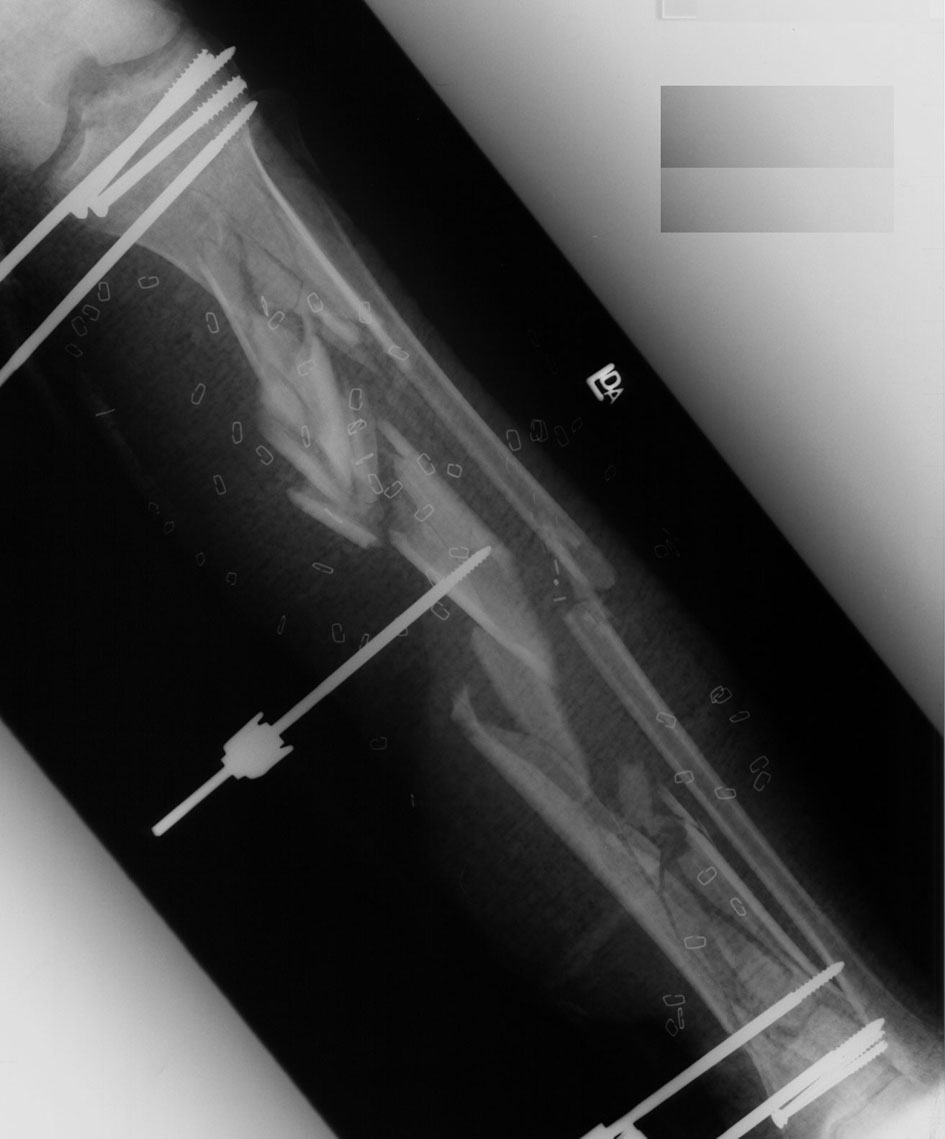

Four Month Followup.Click images to enlarge.

The patient is now 4 months post injury. 2 weeks ago I aligned thefibula with an open IM pin and added 3 transfixation wires to middle pieces.The patient has some but minimal callus despite 1) accordion 2) weightbearing3) electrical stimulation. The soft tissue looks ok but is kind of drippingoff his bone posteriorly like hot wax off a candle. I instituted proneposition 12 hrs/day to make gravity helpful some of the time and this seemsto have improved the situation a bit. A segment of fibula was chopped inpieces and placed posterior to the tibia jct mid distal 1/3 2 weeks ago.Original post-operative film scanned with a Howtech DX-2 ScanMaster (reduced from 144 to 72 dpi, saved @10:1 JPEG compression) Click image to enlarge.

scan courtesy of Dave Ryon, MD, Kingston Diagnostic Center,Kingston, NY